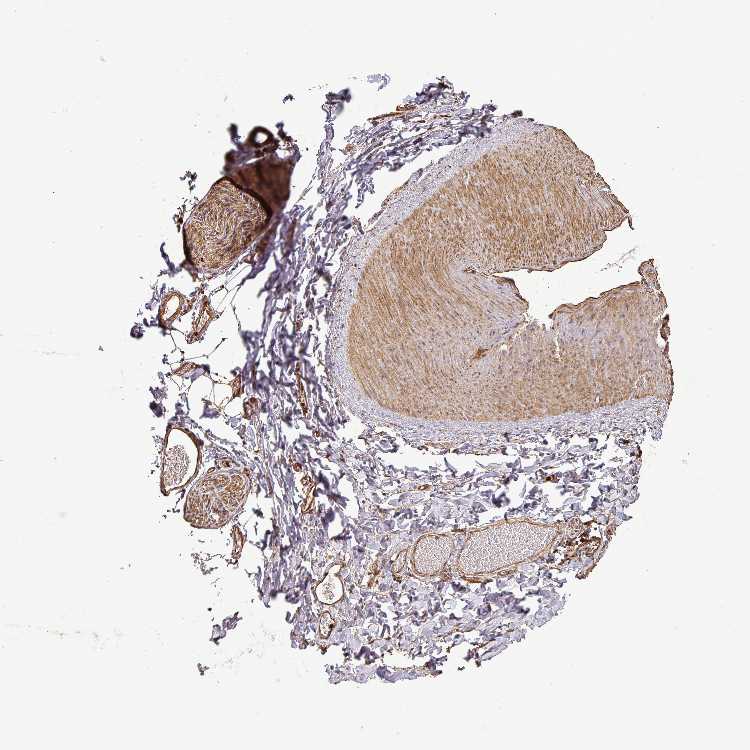

SOFT TISSUE 1 - Antibody stainingi

Antibody staining in the annotated cell types in the current human tissue is reported as not detected, low, medium, or high, based on conventional immunohistochemistry profiling in selected tissues. This score is based on the combination of the staining intensity and fraction of stained cells.

Each image is clickable and will lead to virtual microscopy that enables deeper exploration of all samples and also displays staining intensity scores, fraction scores and subcellular localization as well as patient and tissue information for each sample.

Antibody HPA025018Antibody HPA039473

Chondrocytes Not detectedMedium

Fibroblasts Not detected-